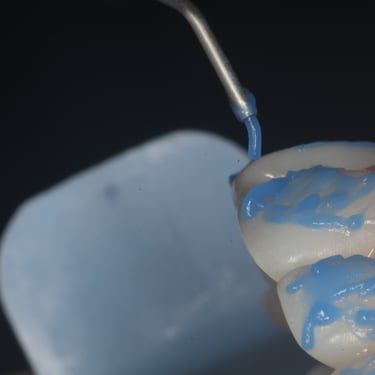

Planejamento digital do implante

O planejamento digital permite fazer a cirurgia sem bisturi e em poucos minutos.